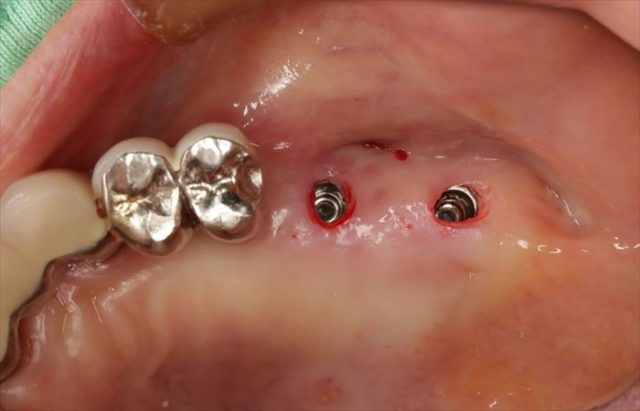

挿入ジグを外しました。

封鎖スクリューで封鎖してインプラントオペの終了です。

出血も最小限で済み、縫合しないため抜糸が不要です。

フラップレスオペは痛みが少ないインプラントオペであることも分かってきています。